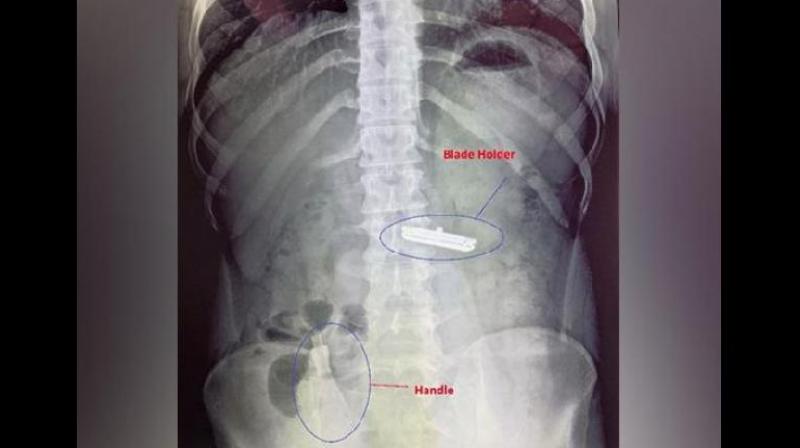

रेज़र दो हिस्सों में निगला गया: ब्लेड होल्डर, जो पेट में फंस गया, और हैंडल, जो बड़ी आंत में चला गया।

रेज़र दो हिस्सों में निगला गया: ब्लेड होल्डर, जो पेट में फंस गया, और हैंडल, जो बड़ी आंत में चला गया। इस स्थिति ने युवक के जीवन को गंभीर खतरा पैदा कर दिया।